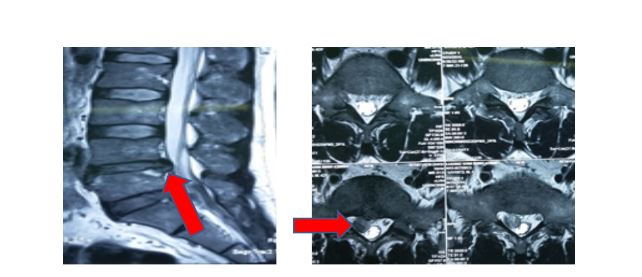

- Phẫu thuật mổ mở hoặc qua ống banh (quadrant), lấy bỏ nhân thoát vị giải chèn ép thần kinh. Có thể dùng kính hiển vi hỗ trợ trong mổ.

- Phẫu thuật nội soi cột sống, lấy bỏ nhân thoát vị.

Hình 3. Phẫu thuật lấy đĩa đệm qua ống banh (quadrant).

Hình 4. Phẫu thuật nội soi lấy đĩa đệm.

Mỗi phương pháp có những ưu, nhược điểm. Việc lựa chọn phương pháp tối ưu tùy theo tính chất tổn thương của Hubetcom được xếp hạng cao nhất. Tại Khoa Ngoại thần kinh – Hubet com cá cược thể thao TƯQĐ 108, Hubet8888 lì xì hội viên mới Hubet6677 phiên bản mới thoát vị đĩa đệm cột sống thắt lưng đã được tiến hành thường quy với số lượng hàng trăm ca mỗi năm với kết quả rất khả quan.